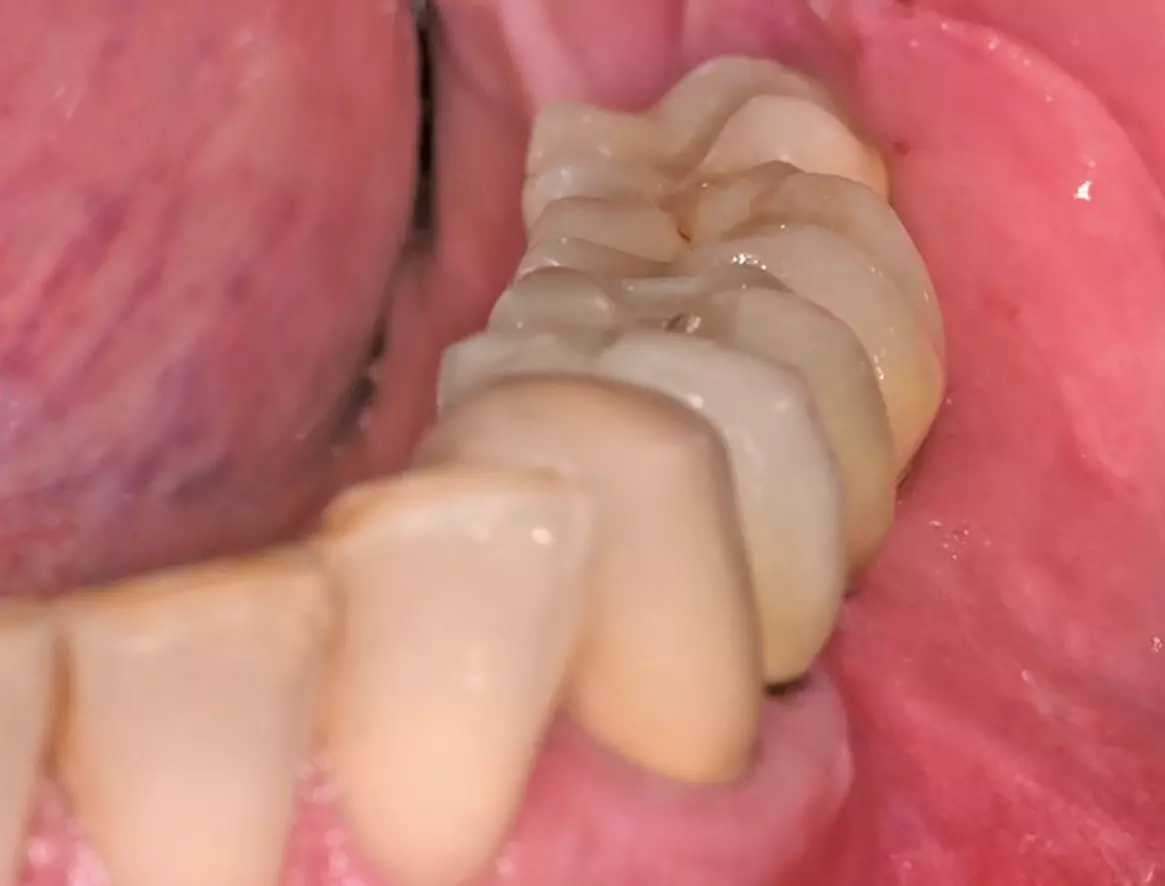

Freilegung und prothetische Versorgung

Die Freilegungsoperation fand nach etwa vier Monaten Einheilzeit statt. Die Implantate zeigten sich regelrecht eingeheilt und gedeckt von einer vitalen Knochenschicht (Abb. 35 und 36). Zur Ausformung der Gingiva wurden die Implantate regio 35 mit einem 4,1 x 3 mm und regio 36 und 37 mit einem 4,5 x 5 mm Gingivaformer versorgt. Zur Gerüsteinprobe (Dentalwerk Nürnberg) drei Wochen nach Eingliederung (Abb. 38) zeigen sich gesunde, reizfreie Schleimhautverhältnisse mit einer ausreichenden Schleimhautdicke (Abb. 37). Abschließend werden die Implantate prothetisch mit einem vollkeramischen Kronenblock (Dentalwerk Nürnberg) drei Wochen nach Freilegung versorgt (Abb. 39a und b). Nach Eingliederung der Prothetik wurde ein abschließendes Kontrollröntgen (Abb. 40) angefertigt, das suffizient eingeheilte Implantate mit mehr als ausreichendem Knochenangebot zeigt.